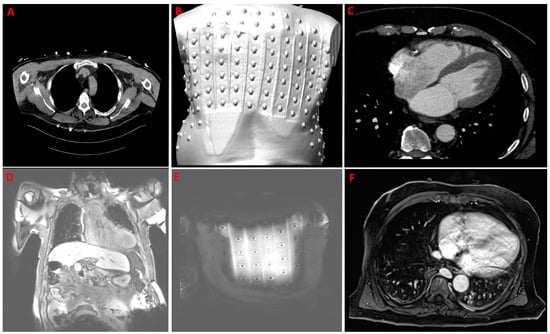

In the second step, the patient underwent cCT (Somatom Definition Edge 126, Siemens AG, Munich, Germany). A low-dose thorax scan (‘LungLowDose’ without contrast and a thickness equal to 2 mm), as a first series, helped to identify the anatomical localization of the metal body-surface electrodes and the individual torso anatomy (Figure 3A,B). An ECG-gated contrast scan of the heart with a thickness equal to 0.75 mm (Figure 3C), as a second series, was achieved using automated intravenous injection of a non-ionic contrast (Solutrast 370—100 mL) during a breath hold. A retrospective acquisition protocol was used. The tomography data were exported in Dicom format.

In case N2, 28 strips corresponding to 224 unipolar body surface MRI-compatible carbon electrodes were placed onto the patient’s torso and used for ECG recording during sinus rhythm (Table 2). Typical clinical PVCs were registered and captured.

The patient underwent cMRI (Magnetom Skyra 3 T, Siemens AG, Munich, Germany). A coronal T1_vibe_fat-sat sequence with a thickness of 2 mm, field of view (FOV) of 500 × 500 mm, and 160 images in the coronal plane before contrast medium administration allowed detection of the full anatomical torso with the applied carbon ECG strips (Figure 3D,E). The transversal T1_vibe_fat-sat sequence with a thickness of 1.2 mm, an FOV of 380 × 380 mm, and 144 images after intravenous administration of contrast medium (Gadovist 0.1 mmol/mL—6 mL) during a breath hold helped to acquire the full heart (Figure 3F).

Figure 3. Upper row: example of recording computer tomography (CT). (A,B)—CT torso acquisition to capture applied metal 8-electrode strips (‘LungLowDose’ scan without contrast); (C)—contrast CT heart acquisition. Lower row: example of recording magnetic resonance imaging (MRI). (D,E)—torso series (t1_vibe_fs_cor_bh) in coronal plane to capture applied carbon MRI-compatible 8-electrode strips; (F)—MRI contrast heart acquisition with t1_vibe_fs_tra_p2_bh_iso_320 sequence.